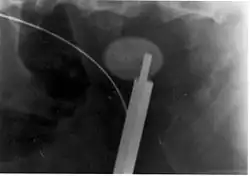

Ultraschallsonde bei der Lithotripsie eines Nierensteins

Am effektivsten ist die Kombination von Ultraschall mit pneumatischen Druckwellen (Lithoklast). Ein beweglicher Stein muss hierzu sanft fixiert, sehr glatte Steine müssen unter Umständen vorher angebohrt werden. Eine Frequenz von 2 bis 4 Hertz ermöglicht eine gleichzeitige Wirkung von Ultraschall- und Schallwellen, Frequenzen um 12 Hz würden nur eine pneumatische Wirkung erreichen, da die Ultraschallwellen kaum mehr mit dem Stein in Kontakt kommen. Nachteilig ist, da ab einer bestimmten Trümmergröße die Steinfragmente so mobil sind, dass sie kaum noch Angriffsfläche für die Wellen bieten.[9]